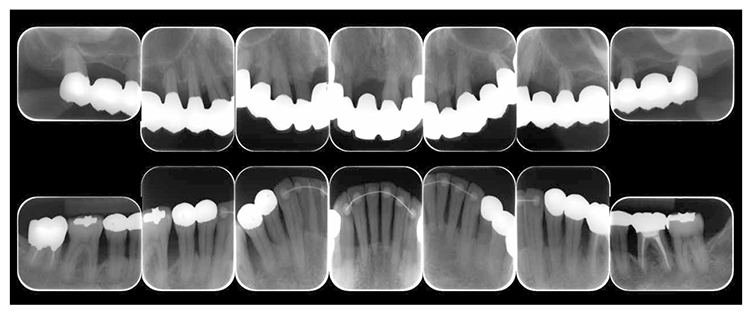

7) Reevaluation testing (December 2003)

At the reevaluation examination after treatment to restore oral function, the color of gingiva was pink, and with prosthetics, intraoral harmony was replicated esthetically and functionally. (Fig.6a). The average PD across the entire jaw was 2.1mm, maximum PD was 4.0mm, the ratio of PD of 3mm or below was 99.3%, no BOP was found and the condition of the periodontal tissue was stable (Fig.6b). In the X-ray, continuity of the alveolar hard line was replicated and the sequence of bone trabeculae was normal, and therefore, the patient transitioned to the SPT phase (Fig.6c).

Fig 6a

(Fig.6a) Intraoral photo after completion of restoration of oral function was completed(2013.4)

Fig 6b

(Fig.6b) Reevaluation and examination after completion of restoration of oral function (April 2013)

Fig 6c

(Fig.6c) Digital X-ray 14 after completion of restoration of oral function (April 2013)